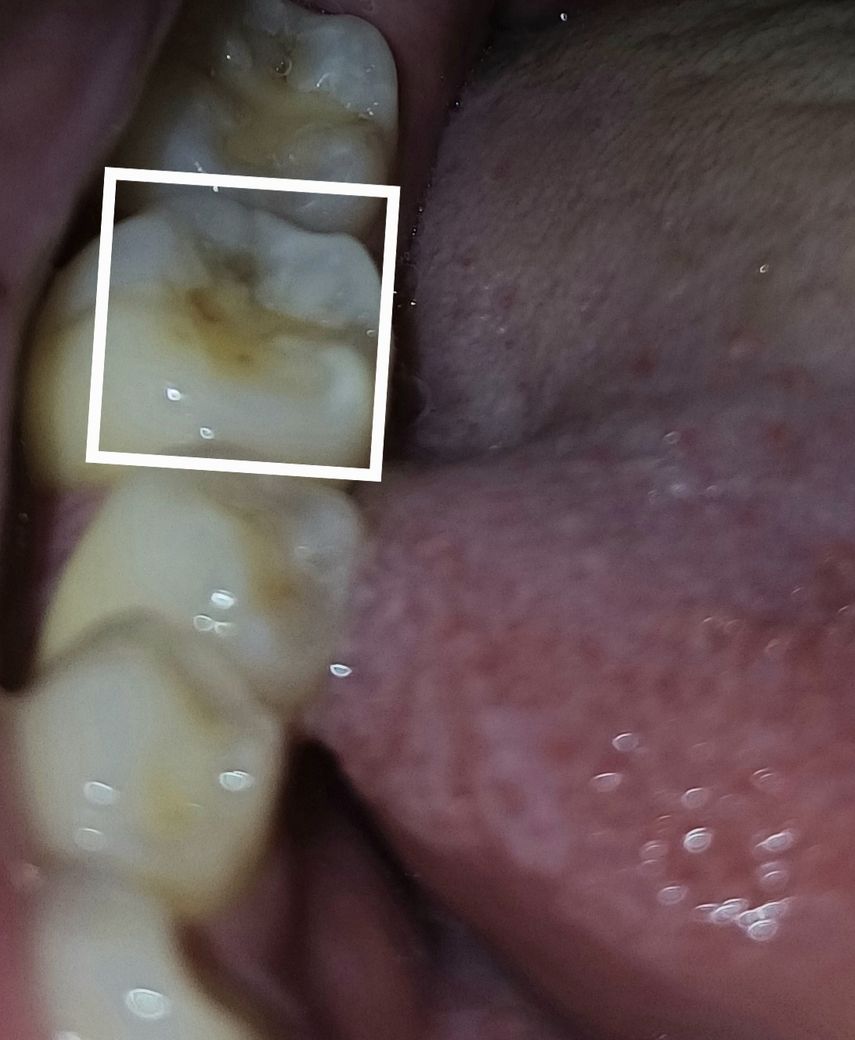

어금니에 약간 검은 색이 올라왔는데 충치인가요?

음식을 씹다가 뭔가 이상한 느낌이 들어서 확인해보니 어금니 쪽에 약간 거뭇거뭇하게 올라와있더라구요.

통증은 없는데 충치 맞을까요??

• 1번 째 사진

사진만으로는 판별하기는 어렵습니다. 착색이 되었을 수도 있고 충치일수도 있습니다만 가능성은 충치가 높아보입니다.

어금니 있는 검은색은 충치일 수도 있고 이전에 충전했던 충전물이 착색으로 인해서 어두워진 것일 수 있습니다. 자세한 확인을 위해서는 치과에서 진료를 받아보는 것이 좋습니다

예전에 치료한 부위 주변으로 착색 및 2차 충치가 생긴거 같습니다. 치과에 가셔서 검진을 받아보시는게 좋을것같습니다.

현재 사진상으로 봤을 때는 이전에 떼운 재료의 변색 가능성도 있어보입니다. 별 증상은 없더라도 6개월에 한번 정도는 치과에 가서 검진을 받아보시는 것을 추천드립니다.